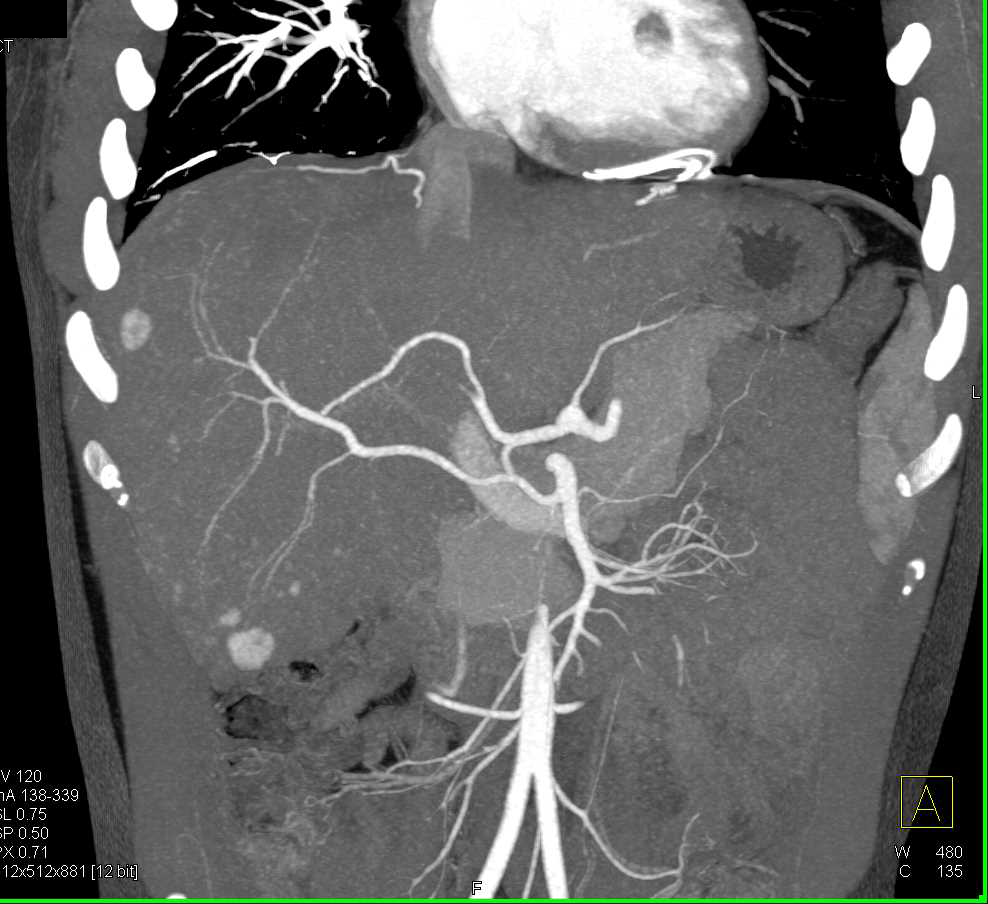

Metastatic Neuroendocrine Tumor to the Liver Best Seen on Arterial Phase Images